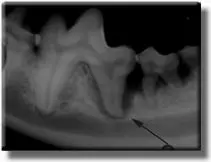

Hidden periodontal problems.

Patient with what appears to be a small periodontal pocket. (arrow)

Radiograph reveals severe bone loss and an abscessed tooth.

Half of the lower jaw bone has been destroyed by infection under the gum line, and the tooth required extraction. This process took years to occur, but was hidden under the gum line, out of view. If this had been caught sooner, the tooth could have been treated as in the case below.